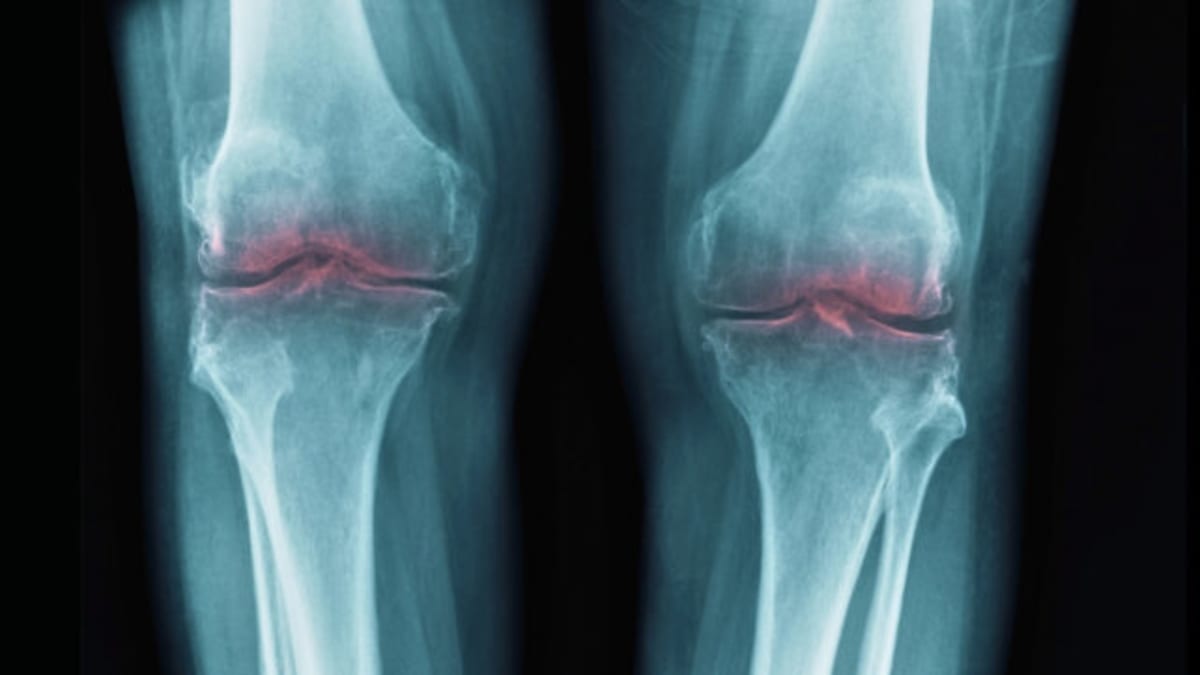

Researchers discovered how to regenerate worn cartilage by blocking a single aging protein, offering hope to millions living with painful osteoarthritis. Multiple breakthrough treatments are racing toward human trials within 18 months.

Osteoarthritis affects over 32 million Americans and severely limits mobility for countless seniors worldwide. Current treatments only manage pain without addressing the root cause, leaving joint replacement as the only real solution for many.